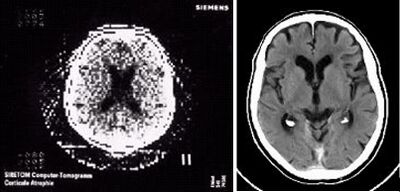

The first CT scanners developed had very low resolution with a resolution of 80 x 80 images and took about 5 minutes to take each scan at every angle, then an additional 2.5 hours to process the images into a single computer processed CT image .5 Modern day CT scanners have a resolution ranging from 1024 x 1024 to 2048 x 2048 and have the ability to take scans in less than a second, allowing from CT images of organs in motion, such as a beating heart.6 The improvement of over time of CT image resolution can be seen in Figure 2 to the right.